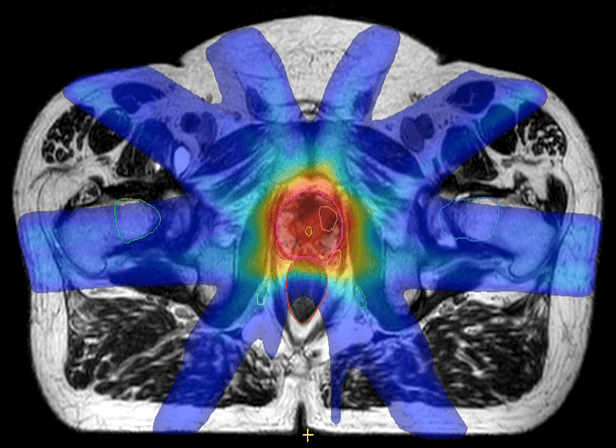

Image (left) shows that the hot dose (red) covers the whole prostate and some of the rectum and urethra. Image (right) shows the hot dose (red) delivered to the intraprostatic cancer only and a lower dose to the rest of the prostate. (Images courtesy of the Netherlands Cancer Institute, NKI).